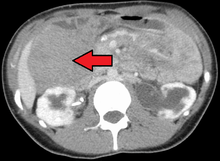

Desmoid tumor as seen on CT scan | |

Aggressive fibromatosis is a rare condition marked by the presence of desmoid tumors. Desmoid tumors can arise in virtually any part of the body, and are tumors that arise from cells called fibroblasts, which are found throughout the body and provide structural support, protection to the vital organs, and play a critical role in wound healing. These tumors tend to occur in women in their thirties, but can occur in anyone at any age. They can be either relatively slow-growing or malignant. However, aggressive fibromatosis is locally aggressive. When they are aggressive they can cause life-threatening problems or even death when they compress vital organs such as intestines, kidney, lungs, blood vessels, nerves etc. Most cases are sporadic, but some are associated with familial adenomatous polyposis (FAP). Approximately 10% of individuals with Gardner's syndrome, a type of FAP with extracolonic features, have desmoid tumors.[1]

Desmoid tumors may be classified as extra-abdominal, abdominal wall, or intra-abdominal (the last is more common in patients with FAP). It is thought that the lesions may develop in relation to estrogen levels or trauma/operations.